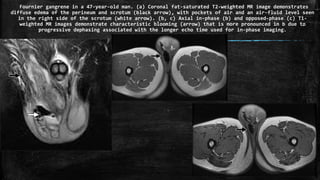

Fournier gangrene in a 47-year-old man. (a) Coronal fat-saturated T2-weighted MR image demonstrates

diffuse edema of the perineum and scrotum (black arrow), with pockets of air and an air-fluid level seen

in the right side of the scrotum (white arrow). (b, c) Axial in-phase (b) and opposed-phase (c) T1-

weighted MR images demonstrate characteristic blooming (arrow) that is more pronounced in b due to

progressive dephasing associated with the longer echo time used for in-phase imaging.

Fournier gangrene ina 47-year-old man. (a) Coronal fat-saturated T2-weighted MR image demonstrates diffuse edema of the perineum and scrotum (black arrow), with pockets of air and an air-fluid level seen in the right side of the scrotum (white arrow). (b, c) Axial in-phase (b) and opposed-phase (c) T1- weighted MR images demonstrate characteristic blooming (arrow) that is more pronounced in b due to progressive dephasing associated with the longer echo time used for in-phase imaging.